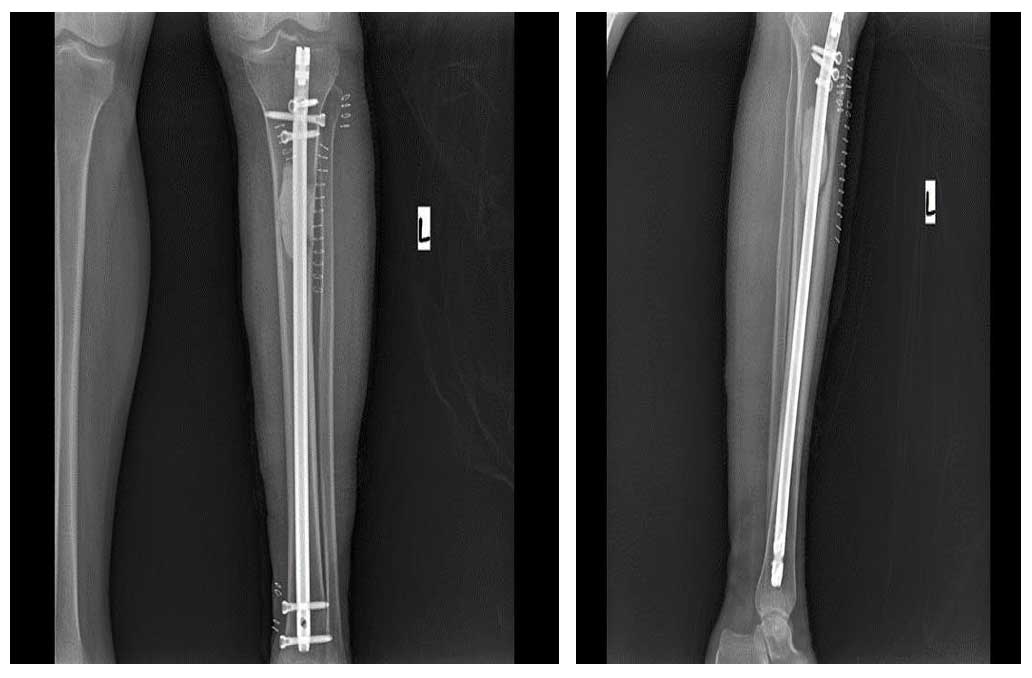

Tümörlü bölge küretaj ile temizlendi, oluşan boşluk kemik çimentosu ile dolduruldu ve kapalı çivileme ile stabilize edildi. Ameliyat başarıyla tamamlandı.

Ameliyat Sonrası: Röntgende tümörün temizlenip oluşan boşluğun kemik çimentosu ile doldurulması ve kapalı titanyum çivi uygulanımı görülmekte.